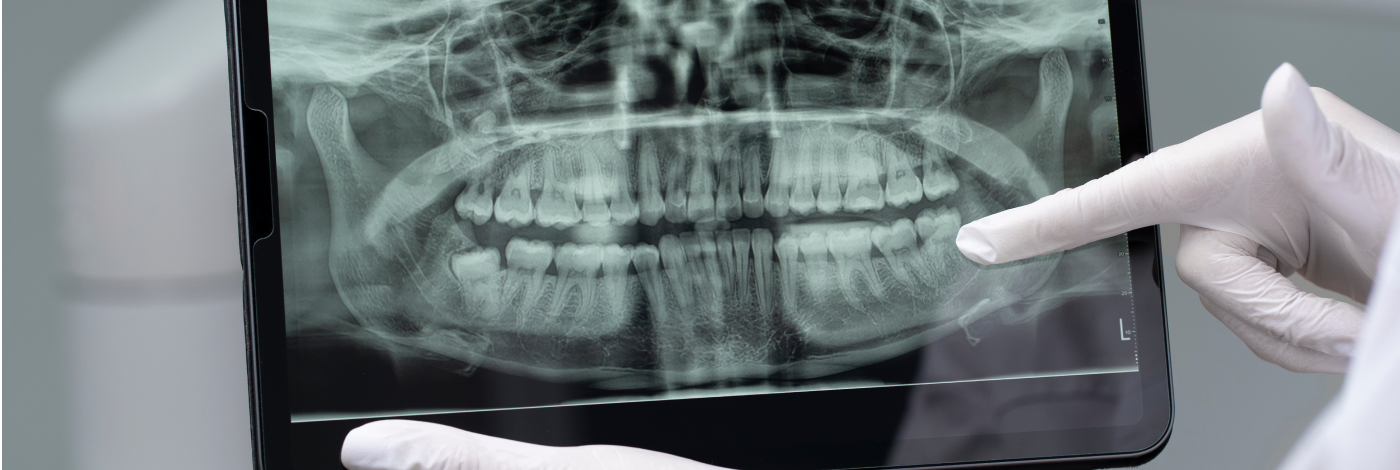

- Radiografia panorâmica: oferece uma visão geral de todos os elementos dentais e suas estruturas anatômicas, sendo frequentemente utilizada em avaliações iniciais, tratamentos ortodônticos, planejamento de cirurgias e odontopediatria.